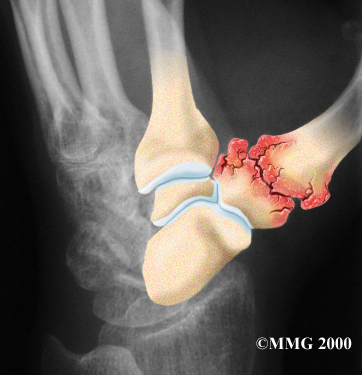

Injury to a joint, such as a bad sprain or fracture, can cause damage to the articular cartilage. An injury to the CMC joint of the thumb, even if it does not injure the articular cartilage directly, can alter how the joint works. After a fracture of the thumb metacarpal, the bone fragments may heal in slightly different positions. The joints may then line up differently. This is also true when the ligaments around the CMC joint are damaged by a sprain. When an injury results in a change in the way the joint moves, the injury may increase the forces on the articular cartilage surfaces. This is similar to any mechanical device or machinery. If the mechanism is out of balance, it tends to wear out faster.

Over many years this imbalance in the joint mechanics can lead to damage on the articular surface. Since articular cartilage cannot heal itself very well, the damage adds up. Eventually, the joint is no longer able to compensate for the increasing damage, and it begins to hurt. Damage has occurred well before the pain begins.